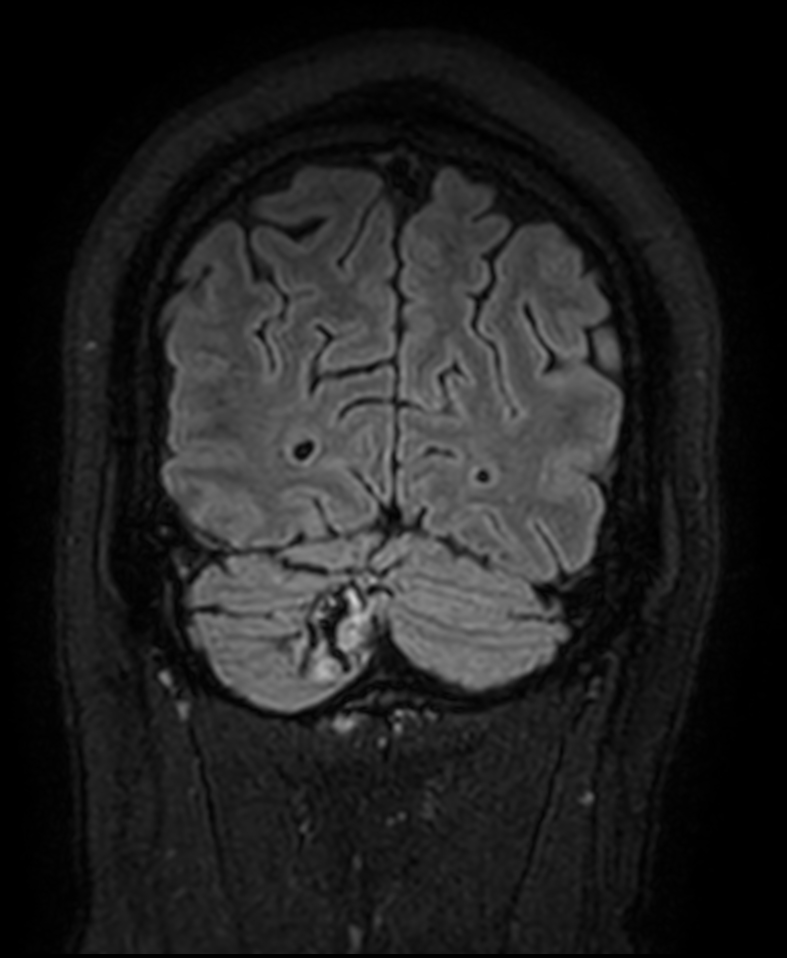

3D T2w FLAIR Compressed SENSE

3D T2w FLAIR (reformat) Compressed SENSE